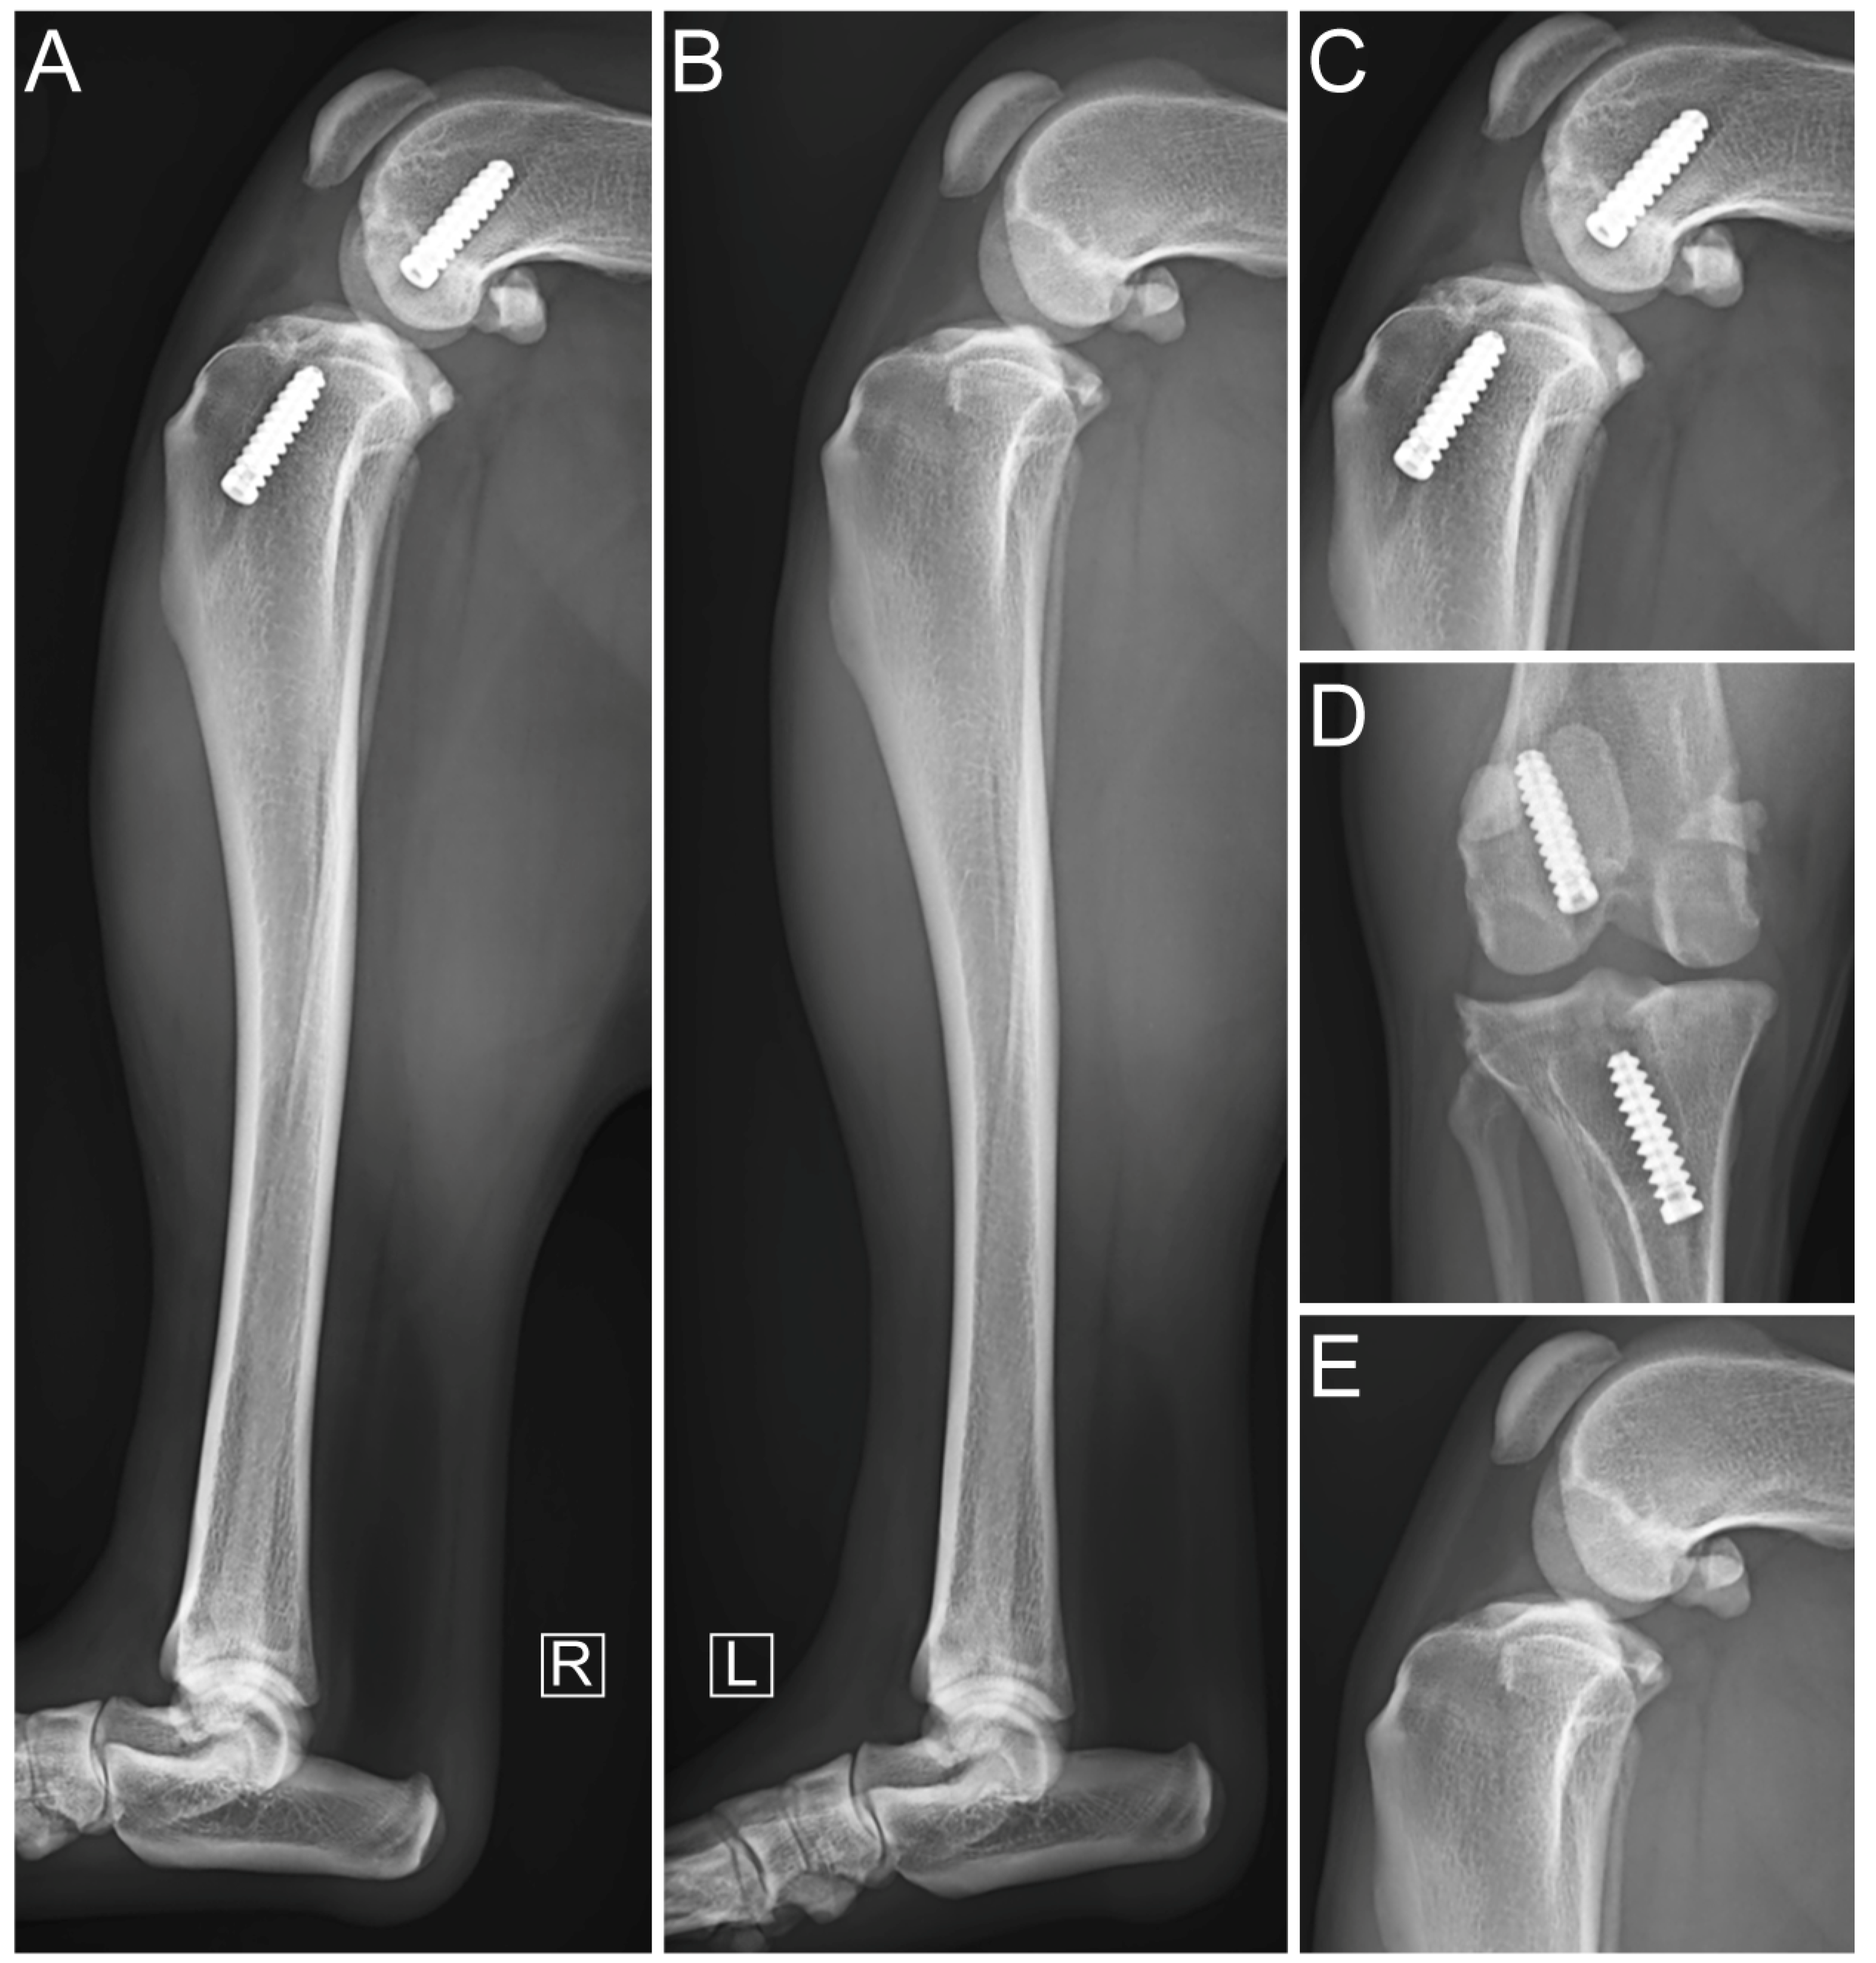

3. Results